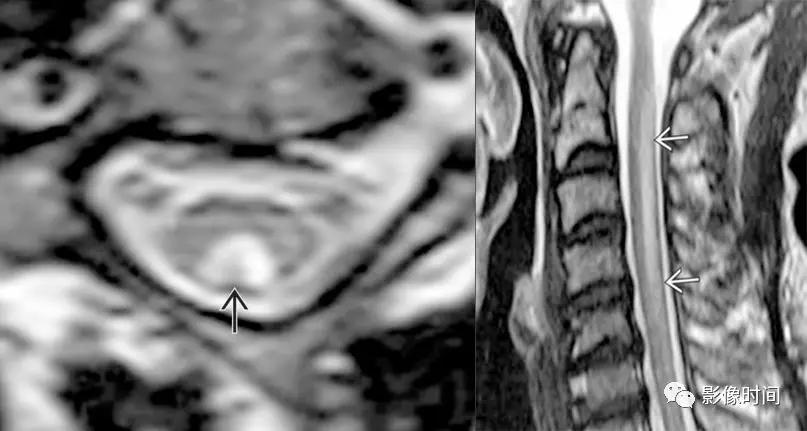

神经脊髓炎谱系疾病(neuromyelitis optica spectrum disorder,NMOSD):是一种由水通道蛋白-4(AQP-4)自身抗体介导的炎性脱髓鞘疾病,青年或中年女性较多见,临床常为双侧视神经炎和脊髓炎导致失明和截瘫,也可累及大脑。

MRI:

脊髓:病灶 T2WI 呈高信号,T1WI 呈稍低信号,急性期出现斑片状或云雾状强化,轴位常位于脊髓中央,长度>3 个椎体长度。亮点征:轴位 T2WI 很高信号的多发斑点,信号高于脑脊液,特异性=97%。

病灶分布于脊髓中央,长度大于3个椎体,亮点征